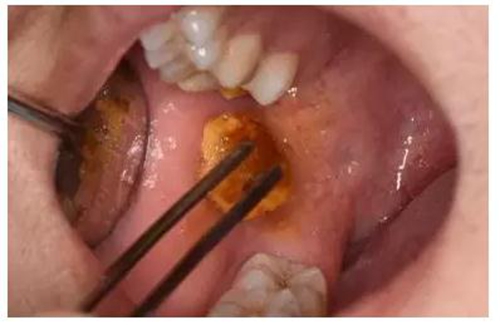

圖15.拔除的48